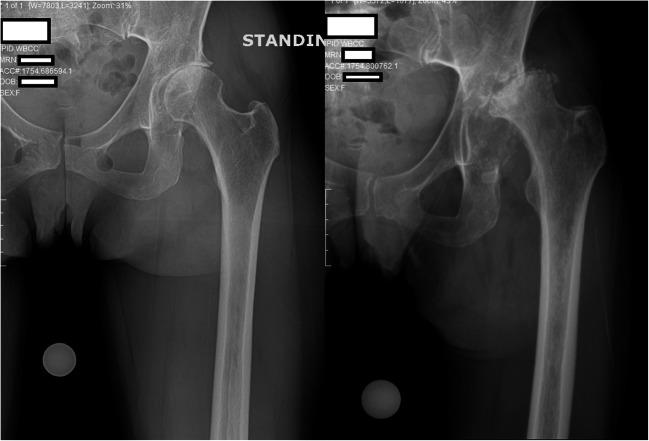

在新冠疫情期间对全髋关节置换术进行分诊

Triaging Total Hip Arthroplasty During the COVID-19 Pandemic.

The purpose of this review was to evaluate the available literature to determine what may be considered urgent indications for total hip arthroplasty, in the unprecedented setting of the worldwide COVID-19 pandemic.

SARS-CoV-2 is a novel coronavirus currently presenting in the form of a global pandemic, referred to as COVID-19. In this setting, multiple states have issued executive orders prohibiting "elective" surgery, including arthroplasty, in order to preserve healthcare resources. However, during this unprecedented reduction in elective surgery, there is likely to be some controversy as to what constitutes a purely "elective" procedure, versus an "urgent" procedure, particularly regarding hip arthroplasty. We reviewed the available literature for articles discussing the most commonly encountered indications for primary, conversion, and revision hip arthroplasty. Based upon the indications discussed in these articles, we further stratified these indications into "elective" versus "urgent" categories. In patients presenting with hip arthroplasty indications, the decision to proceed urgently with surgery should be based upon (a) the potential harm incurred by the patient if the surgery was delayed and (b) the potential risk incurred by the patient in the context of COVID-19 if surgery was performed. The authors present a decision-making algorithm for determining surgical urgency in three patients who underwent surgery in this context. Urgent total hip arthroplasty in the setting of the COVID-19 pandemic is a complex decision-making process, involving clinical and epidemiological factors. These decisions are best made in coordination with a multidisciplinary committee of one's peers. Region-specific issues such as hospital resources and availability of PPE may also inform the decision-making process.

严重急性呼吸综合征冠状病毒2(SARS-CoV-2)是一种新型冠状病毒,目前以全球大流行的形式出现,即2019冠状病毒病(COVID-19)。在这种情况下,多个州已发布行政命令,禁止包括关节置换术在内的“择期”手术,以保护医疗资源。然而,在择期手术前所未有的减少期间,对于什么构成纯粹的“择期”手术与“紧急”手术,尤其是关于髋关节置换术,可能会存在一些争议。我们查阅了现有文献,寻找讨论初次、转换和翻修髋关节置换术最常见指征的文章。根据这些文章中讨论的指征,我们进一步将这些指征分为“择期”和“紧急”两类。对于有髋关节置换术指征的患者,紧急进行手术的决定应基于:(a)如果手术延迟患者可能遭受的潜在损害,以及(b)如果进行手术患者在新冠疫情背景下可能面临的潜在风险。作者提出了一种决策算法,用于确定在此背景下接受手术的三名患者的手术紧迫性。在新冠疫情背景下进行紧急全髋关节置换术是一个复杂的决策过程,涉及临床和流行病学因素。这些决策最好与同行的多学科委员会协调做出。特定地区的问题,如医院资源和个人防护装备的可用性,也可能为决策过程提供参考。

Complex Revisions in Total Hip Arthroplasty Amidst COVID-19 Delays: A Case Report.新冠疫情延误期间全髋关节置换术的复杂翻修:一例报告

J Orthop Case Rep. 2025 Feb;15(2):141-145. doi: 10.13107/jocr.2025.v15.i02.5260.